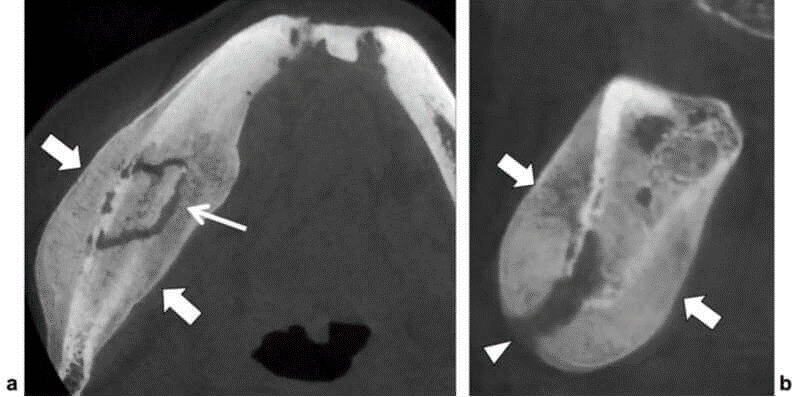

Malformación arteriovenosa en la mandíbula

Una malformación arteriovenosa (MAV) es una malformación vascular caracterizada por comunicaciones anómalas entre arterias y venas sin el lecho capilar normal que se interpone entre ellas. Las MAV de la mandíbula son afecciones extremadamente raras que pueden dar lugar a complicaciones terribles si se tratan sin cuidado. El cincuenta por ciento de todas las MAV...